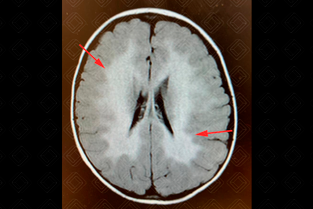

Descrição da imagem: Imagem axial, FLAIR com padrão periventricular em asa em borboleta (setas vermelhas).

• Achados precoces: Redução do sinal em T1 na substância branca profunda; no T2 há um hipersinal confluente periventricular (em forma de borboleta), com preservação de mielina perivenular (padrão tigroide) e, inicialmente, pode haver preservação das fibras em U;